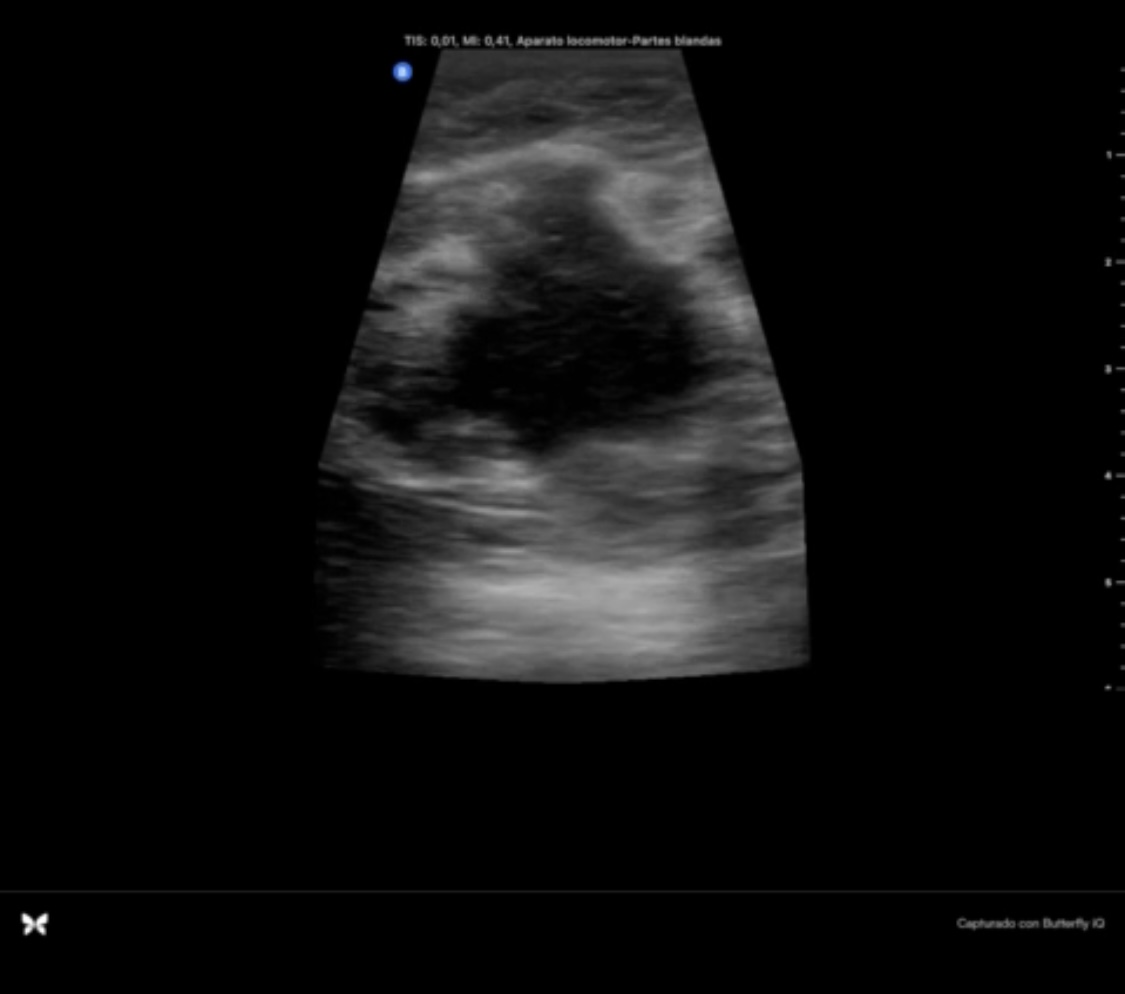

Hallazgos ecográficos

Se objetiva masa hipoecogénica respecto al tejido fibroglandular, heteroecogénica, mal delimitada, más alta que ancha y que no se modifica con la presión de la sonda. En regiones circundantes a la lesión se objetivan lesiones redondeadas, quísticas, que impresionan dilataciones de los conductos galactóforos.

Tras las pruebas complementarias, se confirmó diagnóstico de Carcinoma Ductal Infiltrante de mama izquierda multifocal cT3cN1.